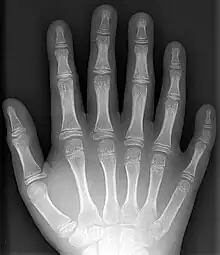

An x-ray of a hand with a supernumerary digit (polydactyly)